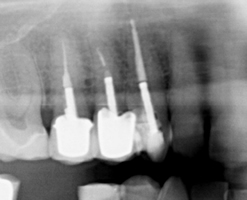

When our dentist for root canal performs a dental root canal treatment in Melbourne, it involves drilling a small hole into the tooth to gain access to the pulp chamber. Once this has been done, the root canal dentist will use specialised instruments to remove diseased and dead pulp tissue as well as clean out the pulp chamber and root canals. The root canals are thoroughly disinfected with antibacterial solutions and are prepared for special dental root canal fillings. The canal space will then be filled and a temporary or permanent filling will be used to seal the access hole.

03-06-01-2 03-06-01-4